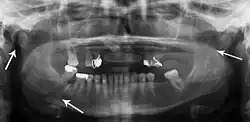

Panoramic radiography

Panoramic radiographs are tomograms where the mandible is in the focal trough and show a flat image of the mandible. Because the curve of the mandible appears in a 2-dimensional image, fractures are easier to spot leading to an accuracy similar to CT except in the condyle region. In addition, broken, missing or malaligned teeth can often be appreciated on a panoramic image which is frequently lost in plain films. Medial/lateral displacement of the fracture segments and especially the condyle are difficult to gauge so the view is sometimes augmented with plain film radiography or computed tomography for more complex mandible fractures.

Research has shown that panoramic radiography is similar to computed tomography in its diagnostic accuracy for mandible fractures and both are more accurate than plain film radiograph.[12] The indications to use CT for mandible fracture vary by region, but it does not seem to add to diagnosis or treatment planning except for comminuted or avulsive type fractures,[13] although, there is better clinician agreement on the location and absence of fractures with CT compared to panoramic radiography.[14]

Panoramic radiograph of a simple mandible fracture of the right mandibular body, minimally displaced. Note that the teeth to the left of the fracture do not touch -